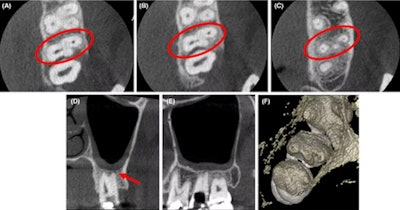

3. Orthodontic wire travels to boy’s brain, causing a seizure

(A) and (B) Coronal and sagittal view of the CT angiogram shows the wire penetrating through the skull floor of a 12-year-old boy. (C) Axial view of CT demonstrates the wire in the temporal lobe and the associated intraparenchymal hemorrhage. (D) Axial bone window CT shows the wire entering through the foramen ovale. Images courtesy of Morgan et al. Licensed by CC BY 4.0.

Imaging aided in the diagnosis of a 12-year-old boy in Texas who experienced a seizure after an orthodontic wire from his braces migrated into his temporal lobe.

After computed tomography (CT) scans and x-rays confirmed the metallic foreign object, which had traveled via the foramen ovale into the temporal lobe, as well as an associated intraparenchymal hemorrhage, the wire was removed without complications. The boy sustained no measurable damage to any structures within or around the foramen ovale, including the carotid artery, which would have been devastating, the authors wrote.

(A-C) Axial CBCT images in the cervical, middle, and apical region of the man’s molar. (D) The coronal section showed the apical split of roots and early periapical radiolucency in the palatal root (red arrow). (E) The sagittal section shows the gouging of the floor. Images courtesy of Marya et al. Licensed by CC BY 4.0.

Imaging aided in managing a man’s atypical root canal anatomy in which the distobuccal canal of his maxillary second molar was close to the palatal root canal with partially fused roots.

From the clinical and imaging findings, clinicians diagnosed the man with pulpal necrosis with symptomatic apical periodontitis and then executed appropriate endodontic treatment, the authors wrote.